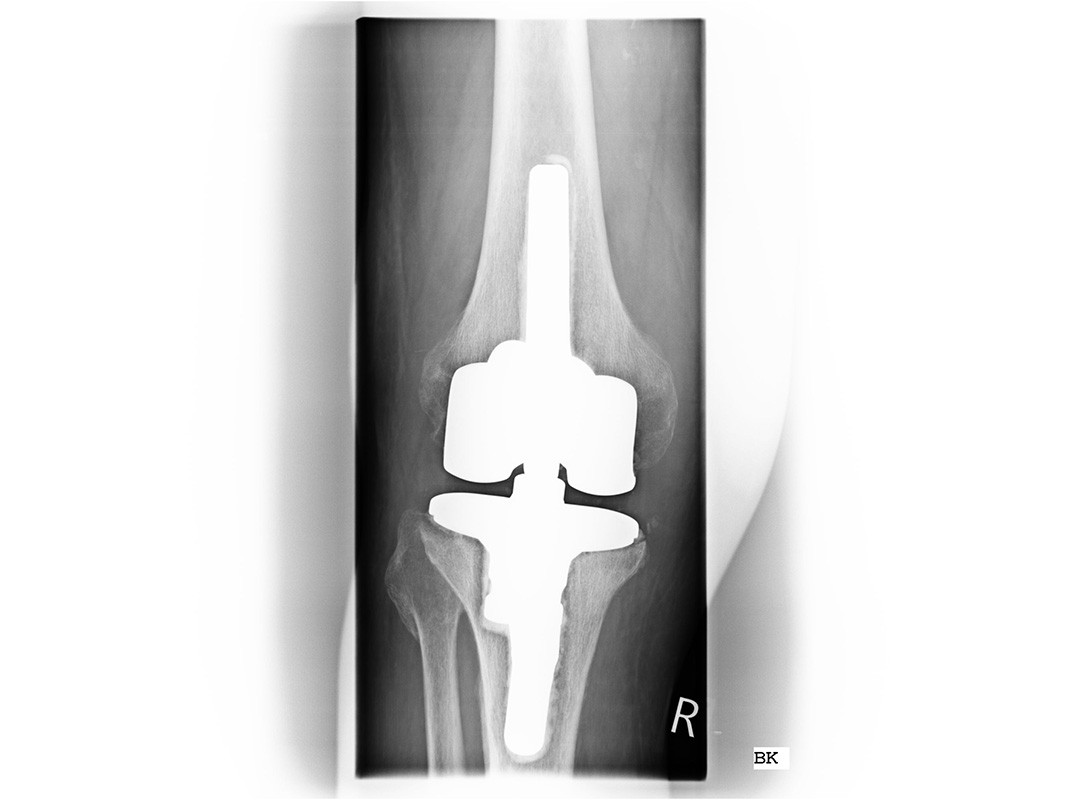

Bei einer starken Fehlstellung und stark gelockerten Seitenbändern des Kniegelenkes muss die Stabilität durch ein Implantat mit Schaftverankerung übernommen werden.

Wechsel oder Teilwechsel einer Knie-TEP

Ein Knieimplantat kann sich nach vielen Jahren lockern, die mittlere Haltbarkeit eines Knieimplantates liegt bei ca. 15 Jahren. Aber auch durch Unfälle oder Stürze kann ein Implantat auslockern. Bei gesicherter Diagnose ist immer eine Wechseloperation zu empfehlen.

Da es bei diesen Operationen auch zu teilweisem Knochenverlust und resultierender Instabilität kommen kann, sind Revisionsimplantate erforderlich mit denen ein erneuter Aufbau des Gelenkes  erreicht wird.